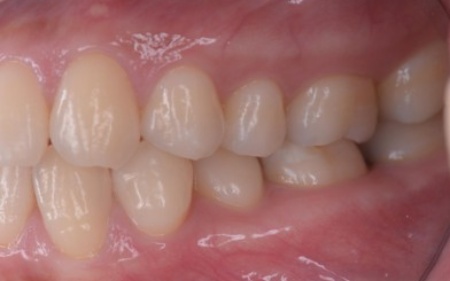

10代女性 乱れた歯並びと噛み合わせをワイヤー矯正で改善した症例

矯正治療終了後は、歯が元の位置に戻ろうとする後戻りを起こすリスクがありますが、治療後15年たった現在も後戻りすることなく、正しい歯並びを維持しています。

15年後の様子